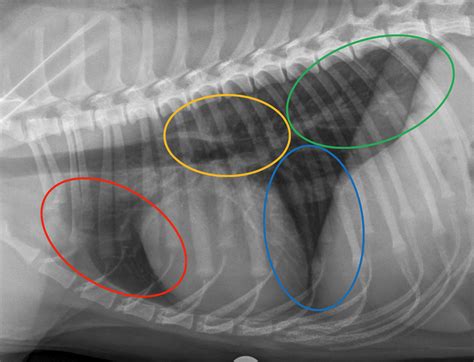

Chest X-rays

Chest X-rays provide a detailed image of the lungs and surrounding structures. They can help identify abnormalities such as inflammation, fluid accumulation, or tumors. X-rays are a non-invasive and relatively quick procedure, making them a valuable tool in diagnosing canine lung disease.